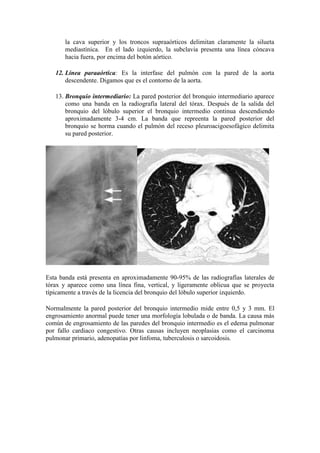

13. Bronquio intermediario: La pared posterior del bronquio intermediario aparece

como una banda en la radiografía lateral del tórax. Después de la salida del

bronquio del lóbulo superior el bronquio intermedio continua descendiendo

aproximadamente 3-4 cm. La banda que repreenta la pared posterior del

bronquio se horma cuando el pulmón del receso pleuroacigoesofágico delimita

su pared posterior.

Esta banda está presenta en aproximadamente 90-95% de las radiografías laterales de

tórax y aparece como una línea fina, vertical, y ligeramente oblicua que se proyecta

típicamente a través de la licencia del bronquio del lóbulo superior izquierdo.

Normalmente la pared posterior del bronquio intermedio mide entre 0,5 y 3 mm. El

engrosamiento anormal puede tener una morfología lobulada o de banda. La causa más

común de engrosamiento de las paredes del bronquio intermedio es el edema pulmonar

por fallo cardiaco congestivo. Otras causas incluyen neoplasias como el carcinoma

pulmonar primario, adenopatías por linfoma, tuberculosis o sarcoidosis.